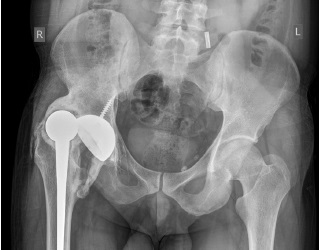

Additional clinical examination based on radiographs revealed dislocation of the endoprosthesis head with the formation of a bone bed of heterotopic ossificates at the anterosuperior edge of the acetabular component, and no signs of loosening of the components were noted (Fig. 2).

Fig. 2. X-ray of the pelvis at admission: dislocation of the endoprosthesis head the with the formation of a bone bed of heterotopic ossifications at the anterosuperior edge of the acetabulum component, no signs of loosening of the endoprosthesis components

According to computed tomography (CT), the acetabular component orientation was 47° of the frontal inclination and 20° of anteversion, the femoral component anteversion was 54°, and the combined version of the components was 101°.

Fig. 4. X-ray of the pelvis after revision surgery